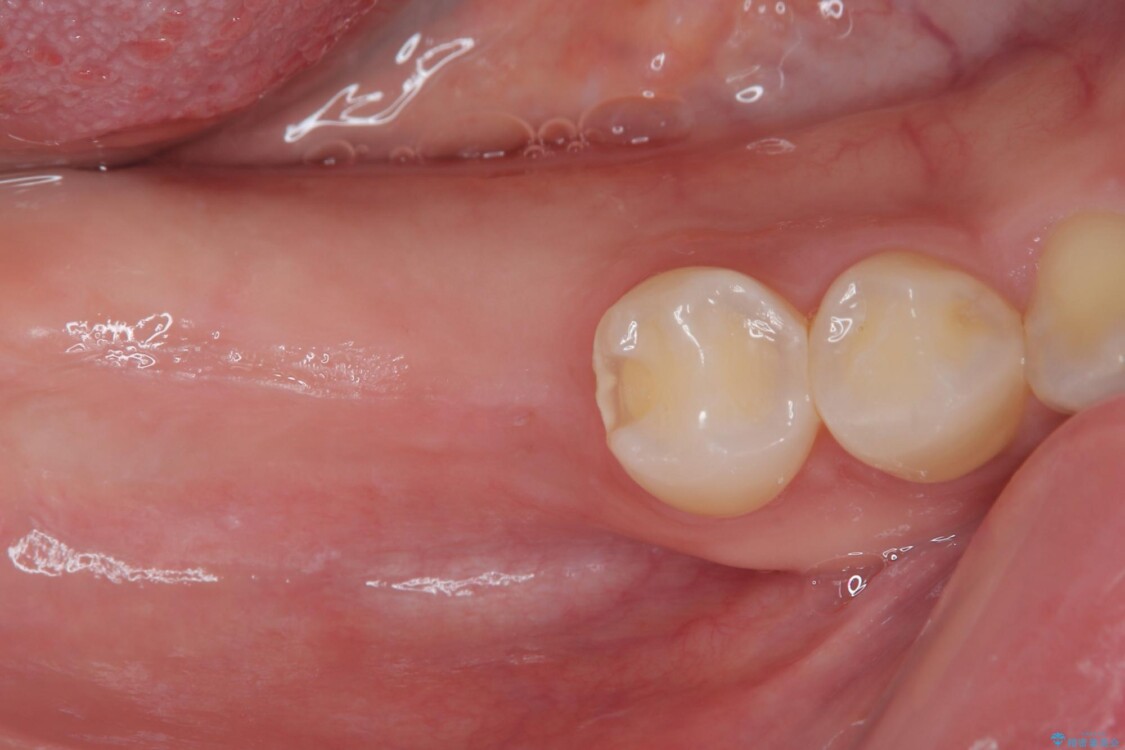

しかし、噛み合わせの相手である右上の第二大臼歯が、長期間噛み合う歯がなかった影響で**挺出(歯が下に伸びてくる状態)してしまっており、このままではインプラントを埋入して被せもの(上部構造)を入れるためのスペースが不足している状態でした。

その後、挺出していた右上第一大臼歯と第二大臼歯に装着されていた銀歯についても、審美性と適合性の向上を目的に、オールセラミッククラウンにやり替えました。

これにより、より自然で美しい見た目と、高い精度の咬合が得られています。

治療後

• 挺出歯を圧下してスペースを確保!目立たない部分矯正で下顎大臼歯にインプラント治療を実現 治療後画像